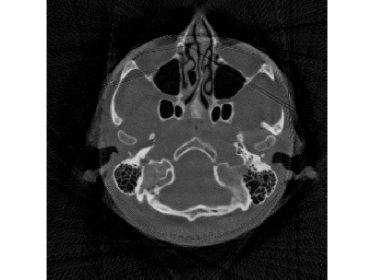

When the detectable range is smaller such that κ=0.4pmax𝜅0.4subscript𝑝\kappa=0.4p_{\max}, saturation becomes worse. Then the performance of FBP and SART, even with water cylinder extrapolation and the ISD scheme, dramatically drops. In practice, this heavy saturation rarely happens and is out of the scope of FBP-WCE. But even with this heavy saturation, the proposed M1bit-CSR-ISD can output a good result. The reconstructed images and enlargements of a region are illustrated in Fig.12 and Fig.13, respectively. In this case, both FBP-WCE and SART-ISD fail to restore the clear outer boundaries of the patient, while M1bit-CSR-ISD is still able to achieve this in a more accurate manner. We further report the saturation detection result in Fig.14, from which one can observe that most of the saturations have been properly detected.

Refer to caption

Figure 12: Reconstruction results for the clinical data (κ=0.4pmax𝜅0.4subscript𝑝\kappa=0.4p_{\max}): (a) ground truth (yellow rectangle is enlarged in Fig.13); (b) FBP-WCE; (c) SART-ISD; (d) M1bit-CSR-ISD.